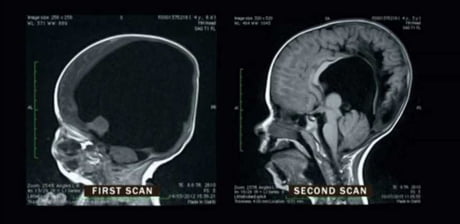

funnyAug 24, 9:00 PMFunnyThese are MRI scans of a boy born with only 2% of his brain and 2 years later. His brain regrew to 80% of its intended size and he only suffers from comparably small cognitive deficits todayfavorite_border0chat_bubble_outline0visibility0send